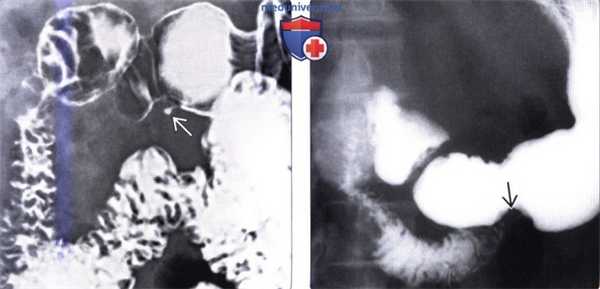

(Слева) На рентгенограмме верхних отделов ЖКТ визуализируется небольшое объемное образование в стенке антрального отдела желудка, слизистая которого не изменена. Центральная «точка» обусловлена наличием рудиментарного протока, заполненного бариевым контрастом.

(Справа) На рентгенограмме верхних отделов ЖКТ в стенке желудка (по большой кривизне в антральном отделе) визуализируется небольшое объемное образование с ровными контурами без центрального вдавления. У 45% пациентов в эктопической ткани ПЖ отмечается центральная ямка, заполняющаяся бариевой взвесью. При отсутствии этого признака эктопическую ткань ПЖ сложно отличить от интрамуральных образований иной природы, таких как метастазы или гастроинтестинальная стромальная опухоль.

(Справа) На аксиальной КТ с контрастным усилением у пациента с жалобами на боль в животе визуализируется кистозное образование в стенке дистальных отделов желудка, как выяснилось после операции — эктопическая ткань поджелудочной железы. В зависимости от соотношения ацинусов, протоков и островковых клеток эктопическая ткань поджелудочной железы может выглядеть однородной или неоднородной, или даже кистозной. (Слева) На рентгенограмме верхних отделов ЖКТ визуализируется небольшое объемное образование в стенке антрального отдела желудка, слизистая которого не изменена. Центральная «точка» обусловлена наличием рудиментарного протока, заполненного бариевым контрастом.